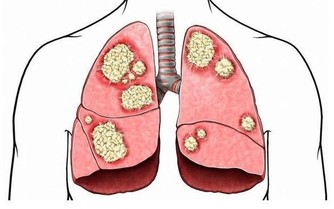

眾所周知,愛滋病是一個危害性極大的傳染病,是由於感染上愛滋病病毒(HIV)而引起的,死亡率很高。有數據表明,全球至少已有3千多萬人死於愛滋病,由此可見愛滋病威力之大。

艾滋病傳播的途徑主要是:與感染者的血液、乳汁、精液、陰道分泌物等多種體液發生交換。

目前,在全世界範圍內仍缺乏根治HIV感染的有效藥物,也無預防艾滋病的有效疫苗,因此最重要的是採取預防措施,其方法是: